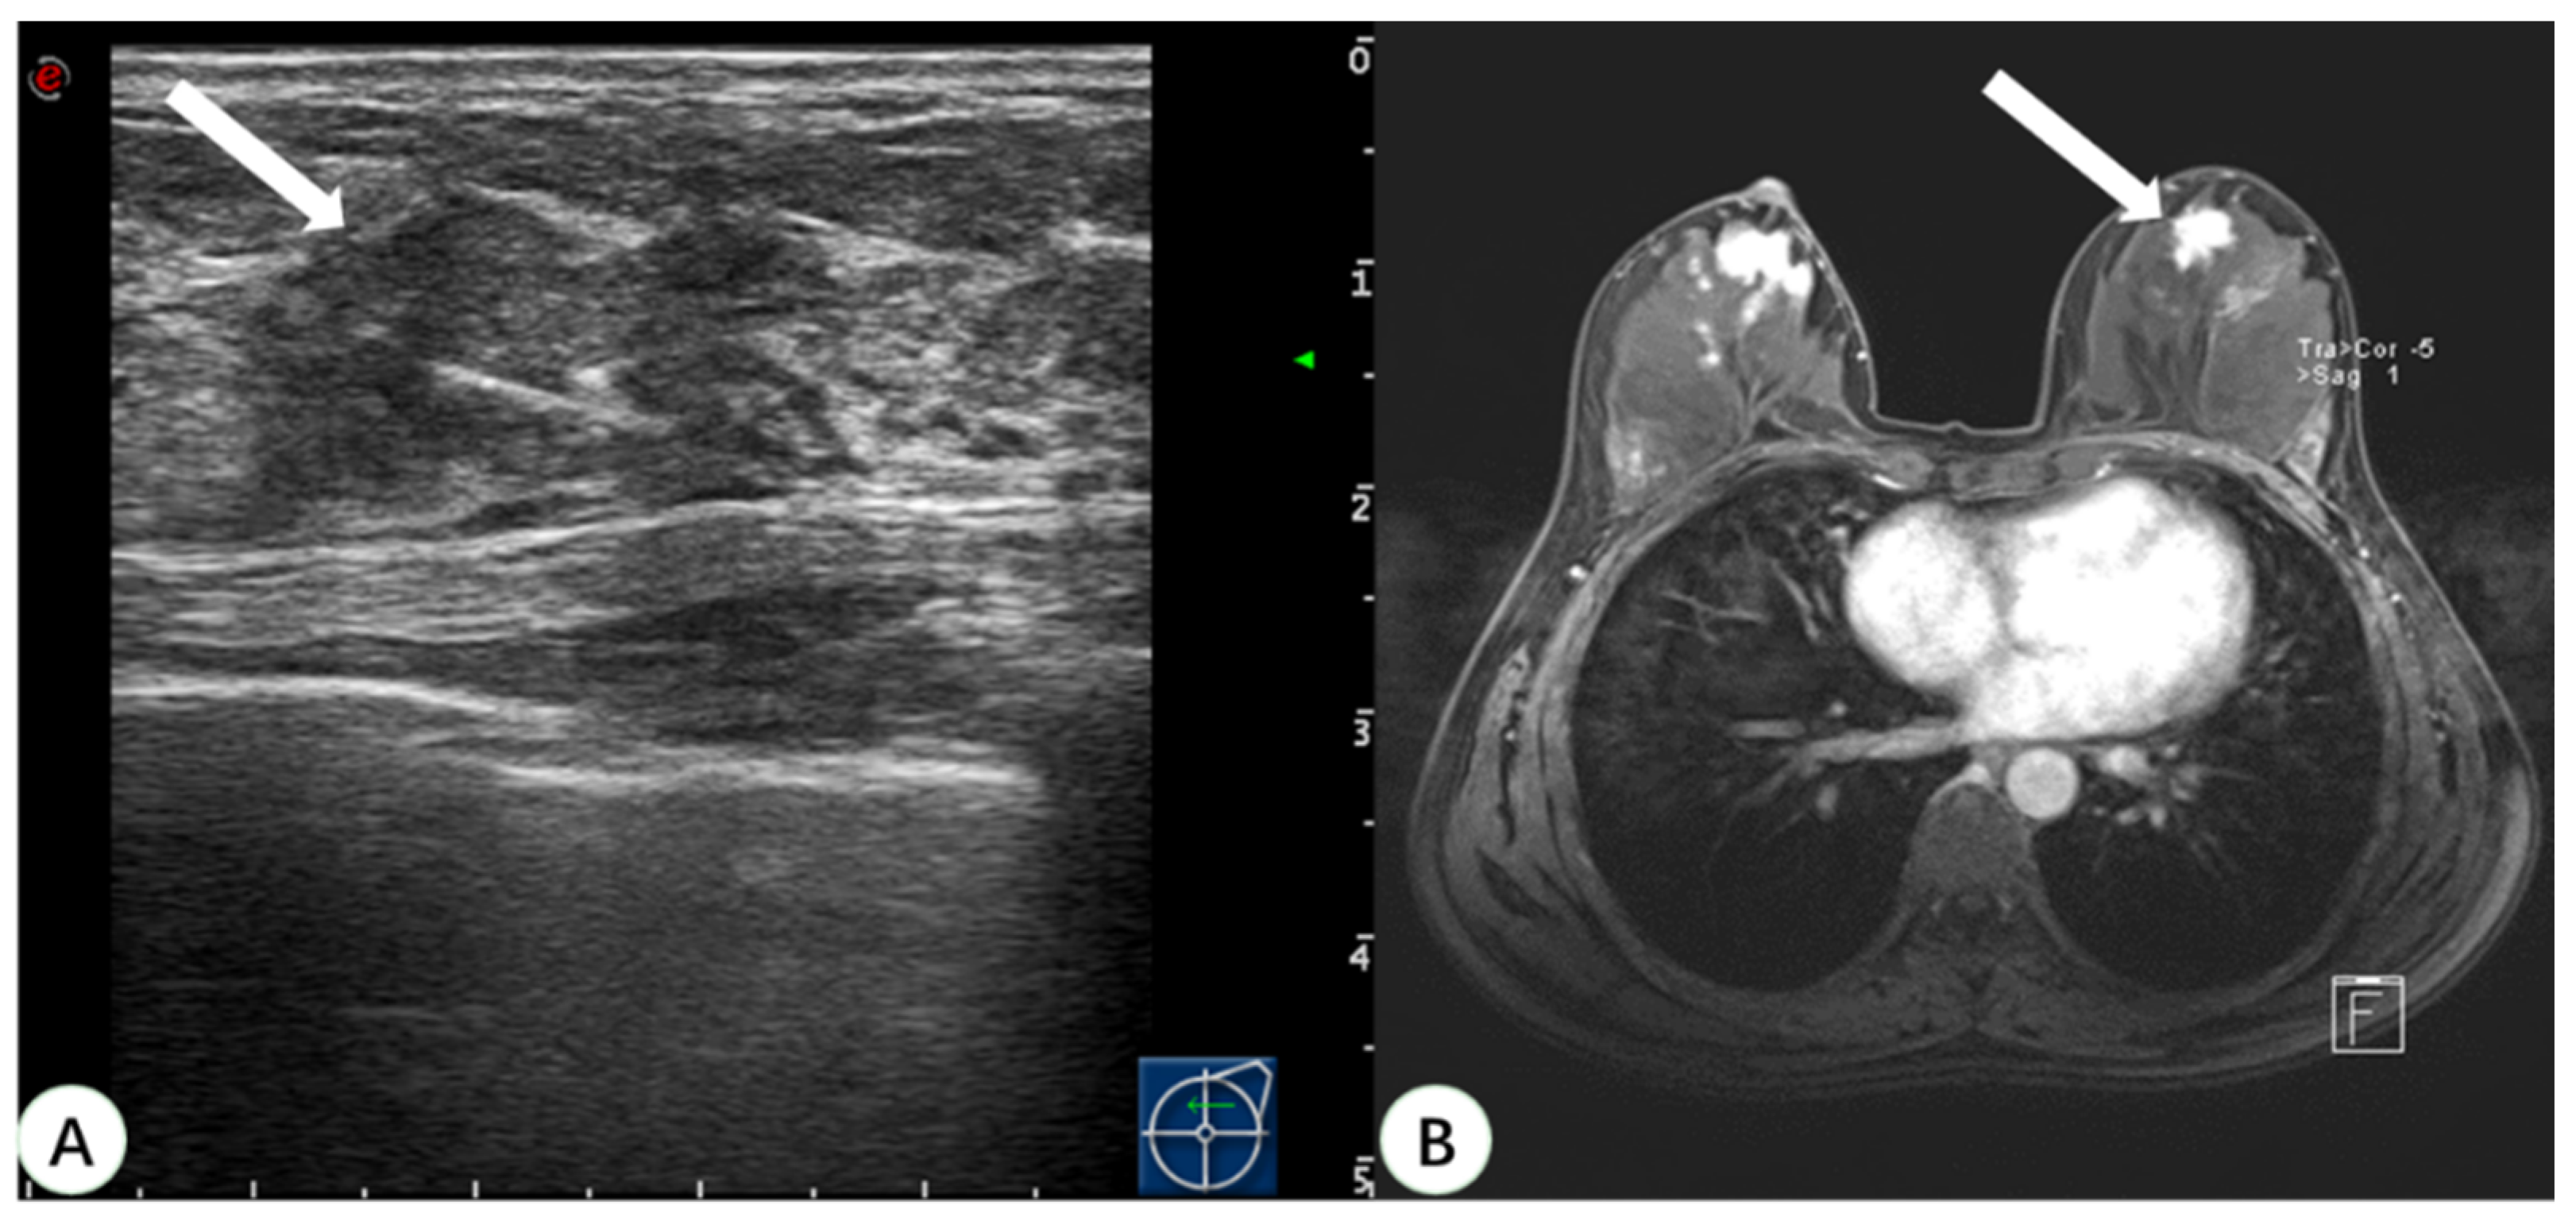

Figure 4.

A 46-year-old woman with dense breast tissue underwent virtual navigation: (A) Real-time US with virtual navigation detected the corresponding lesion (arrow) in the left breast at the 12-o’clock position 2 cm from the nipple, which underwent ultrasound-guided biopsy; (B) CE-MRI showed a suspicious enhanced irregular lesion (arrow) in the upper left breast, undetected at second-look US. Pathology obtained by US-guided biopsy with virtual navigation demonstrated a ductal carcinoma in situ. US = ultrasound; CE-MRI = contrast-enhanced magnetic resonance imaging.